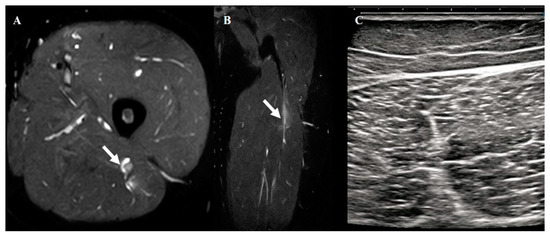

2.4. Hamstring Muscle Diagnosis Using MRI

3.3. Agreement Between US and MRI and Clinical Relevance of Injury Location

| Musculotendinous Junction | 80 |

| Muscle Belly | 90 |

| Tendon | 60 |